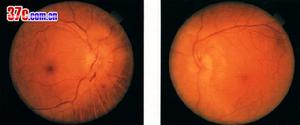

前部缺血性視神經病變2.眼底改變;早期部分或全部視乳頭顏色變淺,邊緣模糊。呈輕、中度水腫。視乳頭及附近視網膜可有少量出血。晚期視乳頭水腫消退,遺有部分或全部視乳頭蒼白,視網膜血管變細。

前部缺血性視神經病變突然發生無痛、非進行性的視力減退。快事為單眼發病,數周至數年可累及另側眼,發病年齡多在50歲以上。眼底檢查:視盤多為局限性灰白色水腫,相應處可有視盤周圍的線狀出血,後期出現視網膜神經纖維層缺損。早期視盤輕度腫脹呈淡紅色,乃視盤表面毛細血管擴展所致。視野缺損為生理盲點相連的弓形或扇形暗電,與視盤的改變部位相識對應。顳動脈炎者可觸及索狀並有壓痛,往往無搏動,可能發生視網膜中央動脈阻塞或顱神經麻痹(特別是第Ⅵ神經麻痹)。